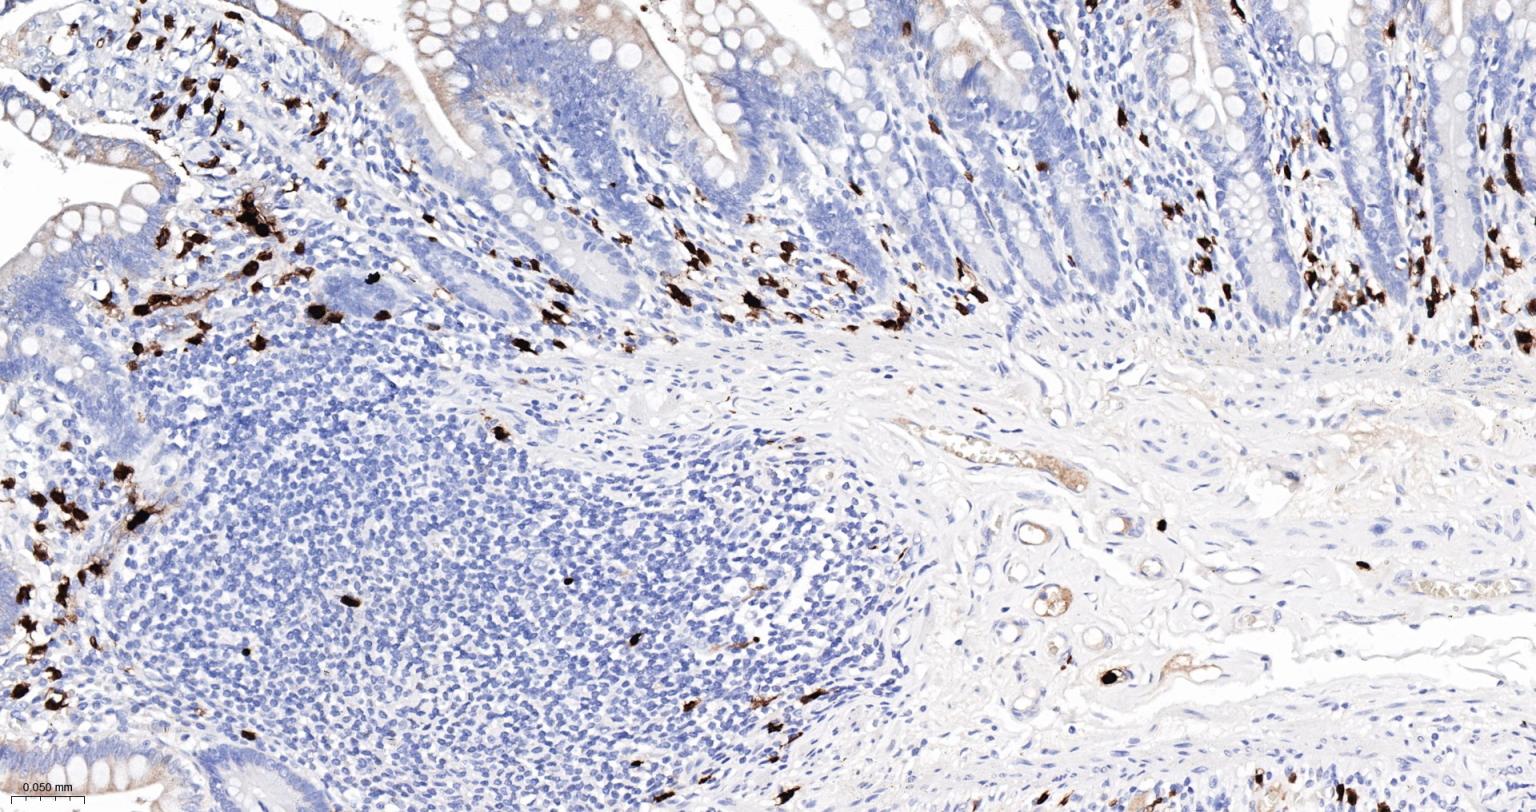

Paraformaldehyde-fixed, paraffin embedded Human Esophagus; Antigen retrieval by boiling in sodium citrate buffer (pH6.0) for 15 min; Antibody incubation with S100A8 Monoclonal Antibody, Unconjugated(bsm-61167R) at 1:200 overnight at 4°C, followed by conjugation to the SP Kit (Rabbit, SP-0023)and DAB (C-0010) staining.